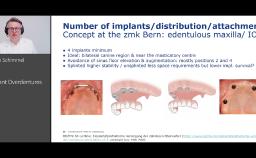

Patients who require dental implants in the esthetic zone often have only a limited amount of bone. Autogenous bone grafting and guided bone regeneration techniques were previously recommended for these patients. Recently, reduced-diameter implants have been widely used in various cases to minimize bone grafting procedures. In order to achieve esthetic and long-term success with reduced-diameter implants, several parameters have to be considered such as implant position, prosthetic techniques, and maintenance protocol. This presentation includes the indications, benefits, and limitations when using reduced-diameter implants in the esthetic zone in various clinical situations.

- discuss the indications for using reduced-diameter implants in the esthetic zone

- recognize the benefits of using reduced-diameter implants in the esthetic zone

- describe surgical and prosthetic techniques to achieve esthetic success with reduced-diameter implants